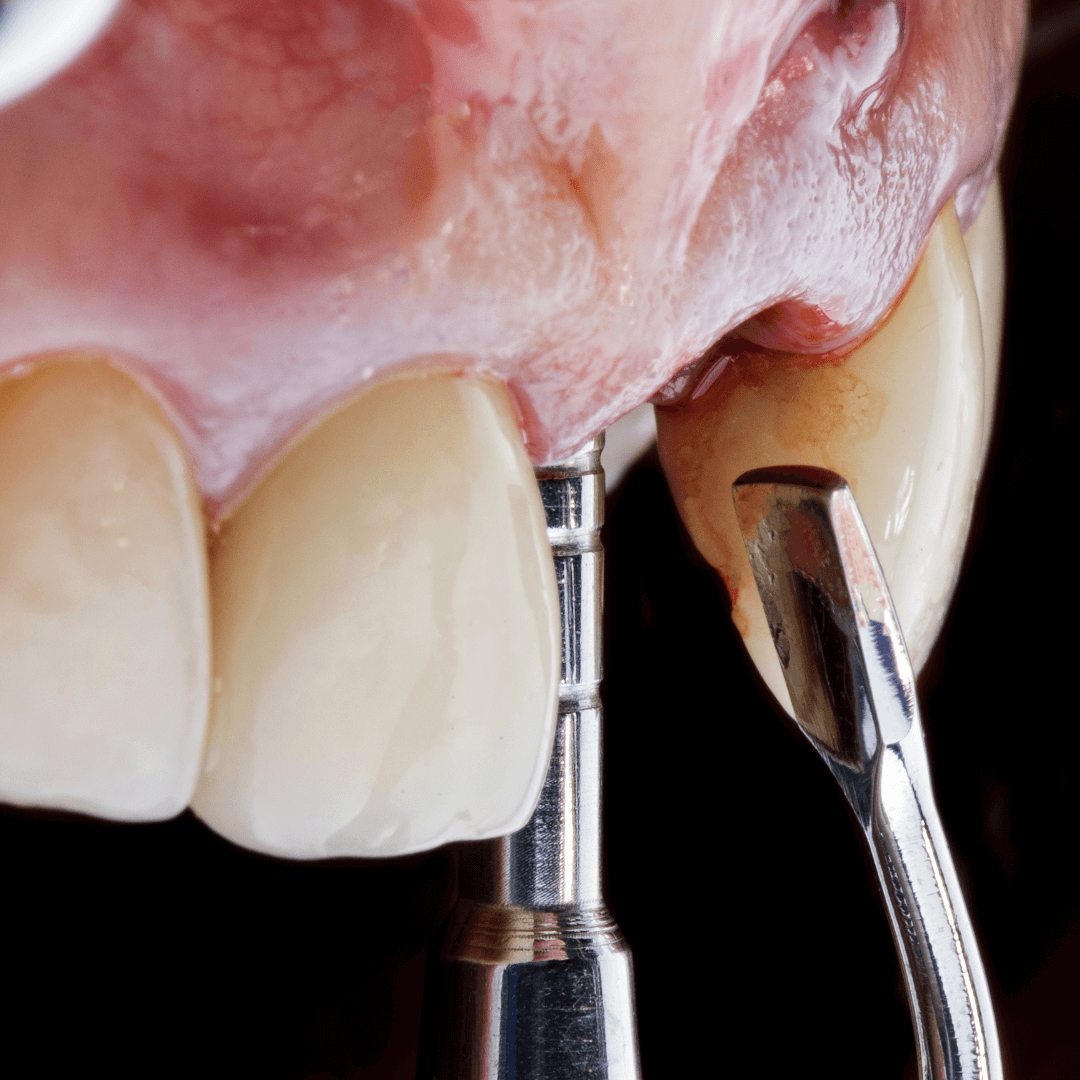

Nakon toga je usledio prvi klinički korak implantološko-protetske terapije – ugradnja implantata. U istom danu nakon ugradnje implantata izrađene su i privremene krunice.

Prilikom izrade privremenih krunica izvršili smo i nivelaciju nivoa mekih tkiva oko prednjih zuba. Na ovaj način smo dodatno unapredili krajnji estetski rezultat.

Nakon perioda oseointegracije smo pristupili izradi definitivnih krunica od cirkonijum-keramike. Izuzetno smo vodili računa i o krunicama na implantima, koje su urađene na cirkonijum abatmentima.